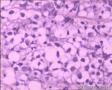

鼻腔新生物

性别年龄80临床诊断

一般病史鼻塞2月

标本名称活检

大体所见小组织三块

恶性肿瘤,IHC分类,首选恶黑、淋巴瘤。

恶性肿瘤,楼上的意见不错,不标记很难分的清,因为肿瘤分化方向不是很显著。

首先考虑恶性淋巴瘤,待IHC吧